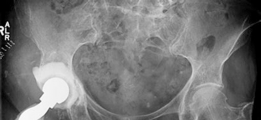

- Standard Radiographs: Anteroposterior (AP) pelvis, frog-leg lateral, and a true lateral of the affected hip are essential. These provide initial assessment of component position, subsidence, osteolysis, and general bone architecture. Stress views may be helpful for suspected pelvic discontinuity.

- An example of a particularly complex reconstruction, potentially involving a larger augment or cage. -

- A final illustrative image, possibly demonstrating long-term follow-up or a specific technical detail.

Paprosky Type IV defects (pelvic discontinuity)

represent the most severe challenge. The literature supports a reconstructive approach that aims to stabilize the discontinuity first, then reconstruct the acetabulum.

- Techniques include plates across the discontinuity (e.g., hook plates, reconstruction plates), anti-protrusio cages (e.g., Kerboull, Burch-Schneider), and increasingly, modular metal augments used in conjunction with these systems or custom triflange implants.

- Studies by Berry et al. (2005) and Jahng et al. (2018) highlight the improved outcomes achieved with stable fixation of the discontinuity, often involving posterior column plating, and a well-fixed revision cup. Modular augments play a crucial role by bridging defects and providing a robust platform for cup fixation within the stabilized pelvic frame.